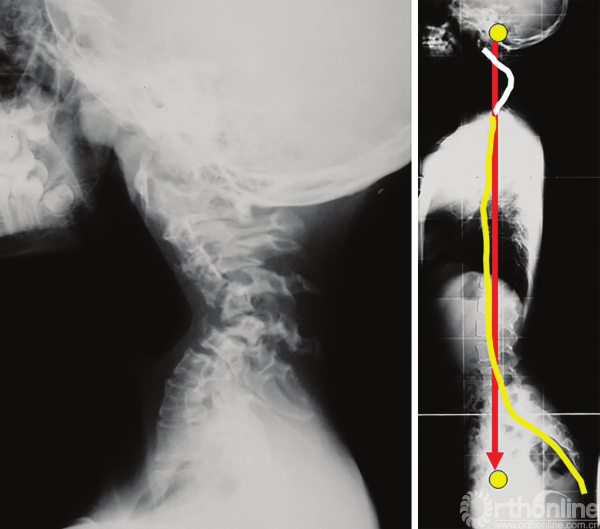

图3-39 神经纤维瘤病患者伴有颈椎严重后凸的脊柱力线,可以注意到胸椎变平以获得外耳道与股骨头之间力线的最佳匹配

向下对线很少见,在神经纤维瘤病伴严重的颈椎后凸畸形,可观察到较少见的向下对线,导致胸椎平背畸形(图3-41)。

本章节讨论了从头到足的脊柱平衡状态,C7铅垂线对于平衡的判定时常不准确,因为这种方式没有考虑到头部对于整体平衡的影响。把颅骨和骨盆看作是一个整体对于研究平衡状态至关重要。

因此,我们可以通过评估外耳道(头骨的重心)和股骨头(股骨头中心,几乎是骨盆的中心)的连线来实现。Gangnet等[28]证明了这两个点(外耳道和股骨头)在正常骨盆形态和处于伸膝状态(完美平衡)的健康受试者中是垂直对齐的。

而对于通过骨盆后倾代偿平衡的患者,股骨头中点会移动到外耳道点的前下方,随后膝关节屈曲,躯干后移,最终胸椎后凸角度减小,有时还会出现上位腰椎向后滑移。PI角大的人群骨盆后倾的能力更强。

Sénégas等[15]讨论了使用踝关节过伸的方式来纠正前方失平衡的方法。尽管有时整个过程对患者来说往往是难以忍受的,但是当从外耳道引下的垂直轴自然落在股骨头前面时,我们把这称为前方失平衡。

外耳道-股骨头垂直对齐可能在某些疾病中持续很长时间,这使得作者定义了向上或向下对线,可用于保持活动度的脊柱节段,主要是颈椎。